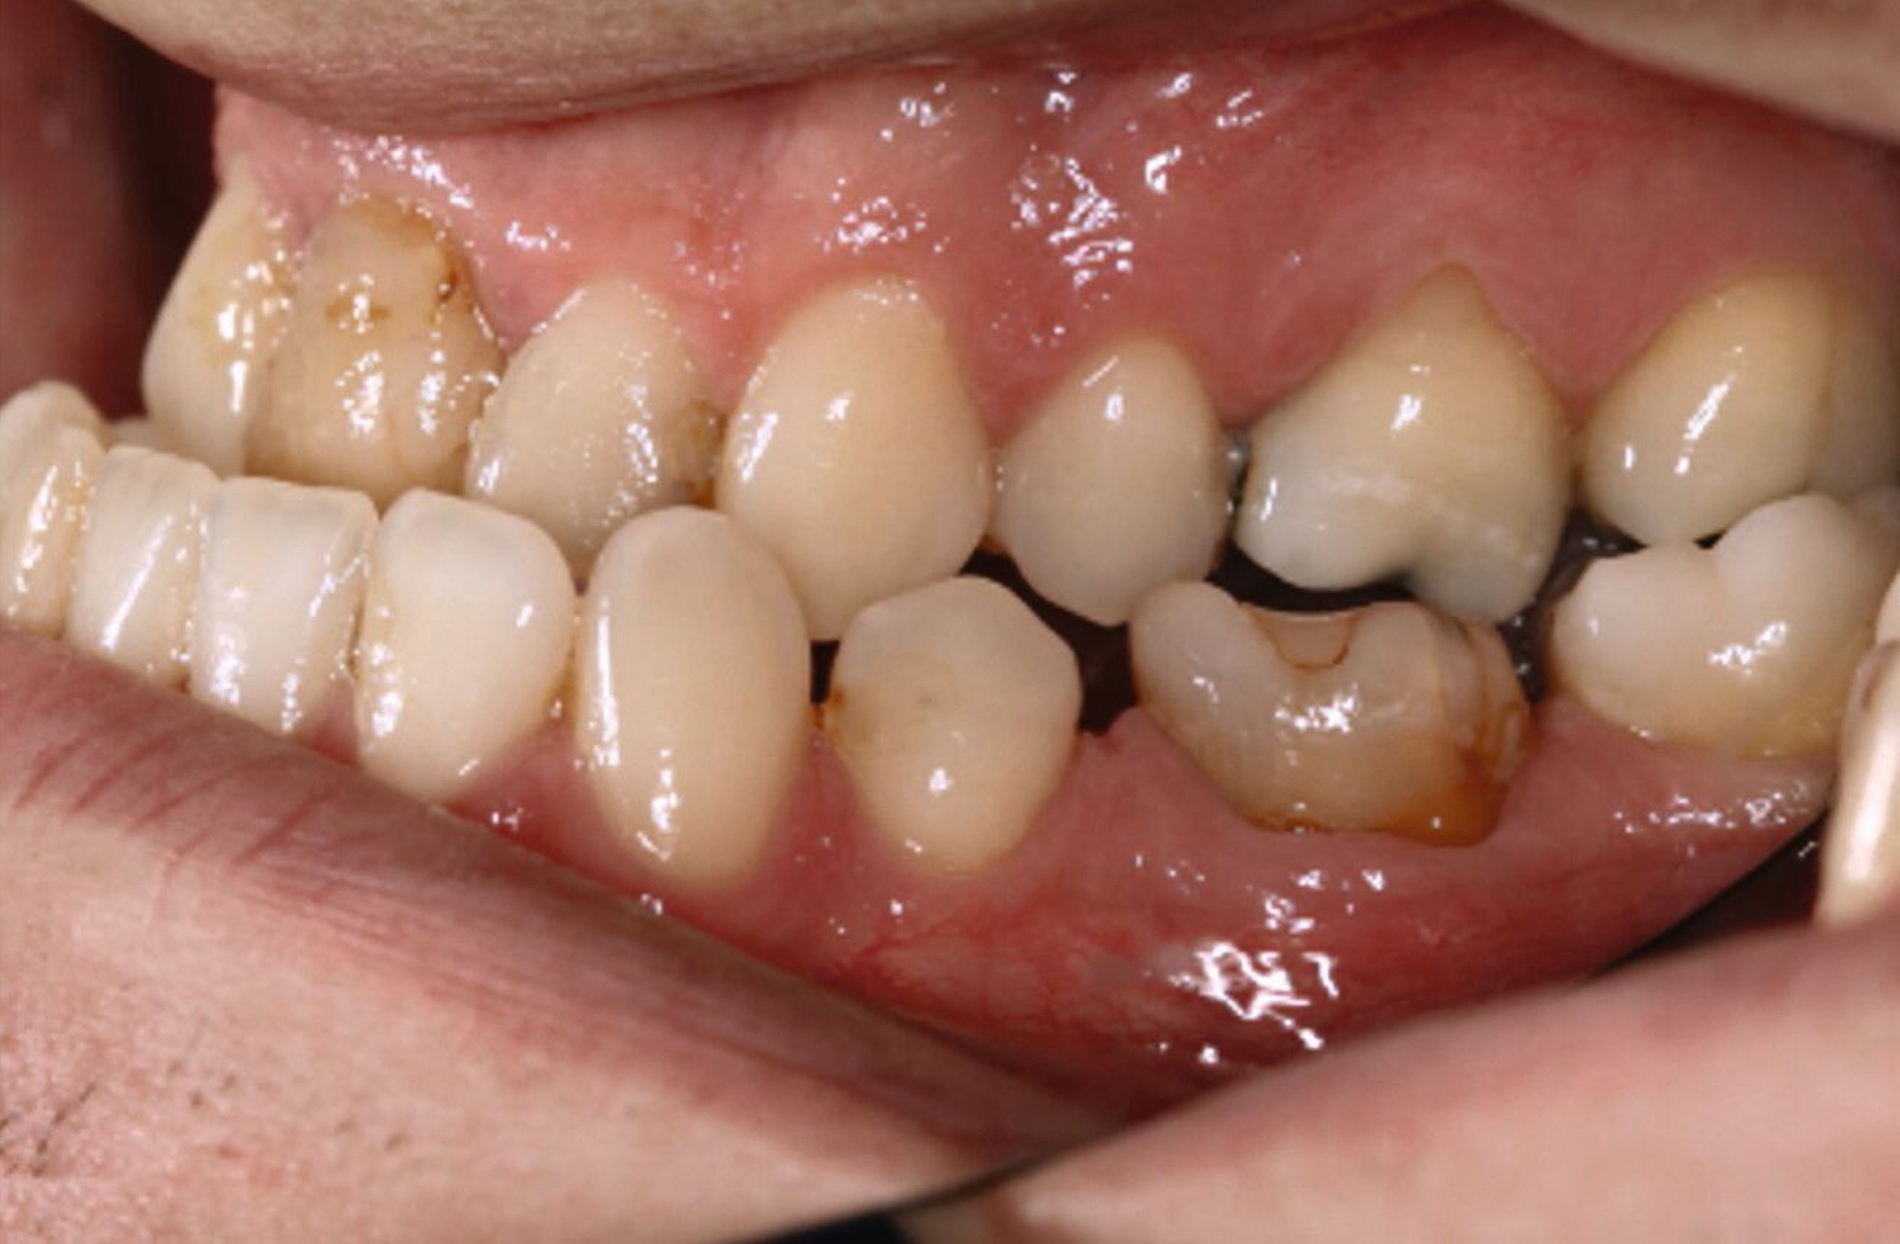

Ein 25-jähriger Patient stellte sich mit dem Wunsch nach Optimierung seines Erscheinungsbildes und seiner Kaufunktion in der kieferorthopädischen Praxis vor (Abbildung 1). Klinisch zeigten sich eine Angle-Klasse-III-Verzahnung mit einer 3/4 Prämolarenbreite Mesialokklusion beidseits und ein zirkulärer Kreuzbiss von 18–12/48–41 und 21–28/31–37. Es lagen ein negativer Overjet von -6,7 mm und ein Overbite von 5,1 mm vor. Eine Mittellinienverschiebung wurde sowohl im Oberkiefer – mit einer Abweichung von 4 mm nach rechts – als auch im Unterkiefer – mit einer Abweichung von 3 mm nach links – diagnostiziert (Abbildungen 2 und 3).

Aufgrund einer hohen Kariesanfälligkeit und einer klinisch floriden Parodontitis waren bereits mehrere Zähne des Patienten extrahiert worden, darunter 16, 11, 25, 38, 35, 45 und 46. Die mesiale Kippung und Aufwanderung der angrenzenden Zähne ließ vermuten, dass der Zahnverlust zeitlich weiter zurücklag. Aufgrund der reduzierten Langzeitprognose des Zahnes 11 entschieden wir uns gemeinsam mit dem Patienten für eine Ausgleichsextraktion des Frontzahns.

Außerdem wurde vor der kieferorthopädischen Intervention die Parodontitis vom Hauszahnarzt behandelt, so dass im Anschluss eine Multiband-Apparatur im Ober- und im Unterkiefer eingesetzt und die Zahnbögen nivelliert werden konnten. Dabei wurden die seitlichen Schneidezähne 12 und 22 anstelle der Zähne 11 und 21 lückig eingeordnet. Die Lücken in Regio 35 und 45 wurden für eine spätere Versorgung vorbereitet.